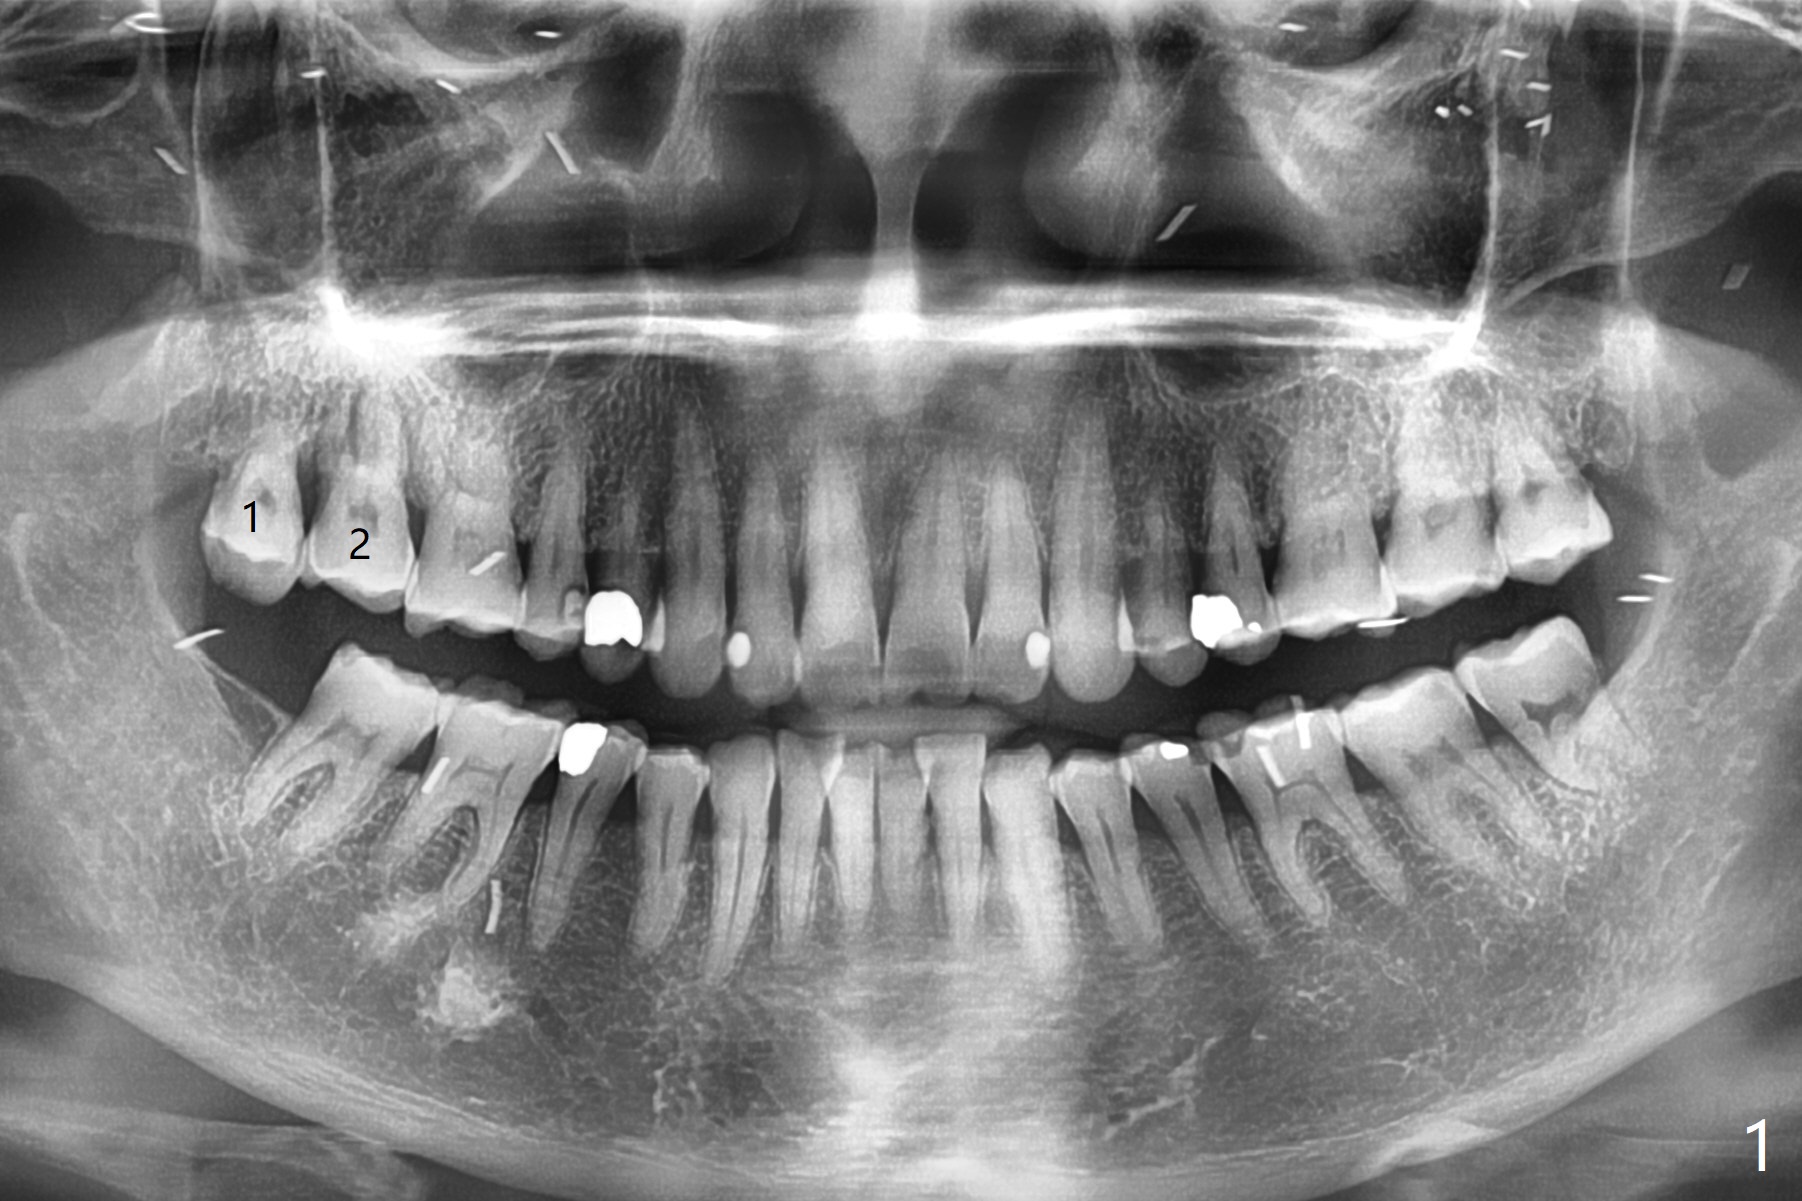

59岁女两年前就诊,主诉右上7,8之间食物坎塞,没有注意7骨质吸收(图一),以为是8过度延申所致拔除,而且远中颊侧,腭侧根断裂(间接说明咬合力大),前者拔除,而后者滞留。如果不拔除,现在支撑导板多好。两年后病人认为断根长出来,其实腭侧根尖仍在骨中(图二(半年前拍摄):箭头),而7骨质吸收更严重,松动2度,怀疑根裂(咬合力大)。同时病人可能有骨质疏松,拔除即刻种植,基台一定要短,一旦牙槽窝愈合,考虑取出临时牙冠,减少微动。取模前,进行渐进性负荷。术前服用Z Pack,准备上颌窦提升,PRFx2。CT显示上颌窦提升不需要,植体可以植入腭侧窝(图三)。 CT冠状切面(图四),矢状切面(图五)显示必须使用长袖的基台(粉红色)固定粘性骨粉(红色),这样植体(绿色)稍微可以种得浅些。箭头:cotton roll(颊侧牙龈沟)。为了让病人在制作导板时舒服些,利用邻牙做冠外固定7松动牙(III)。7颊侧软组织缺失(图六:*)。